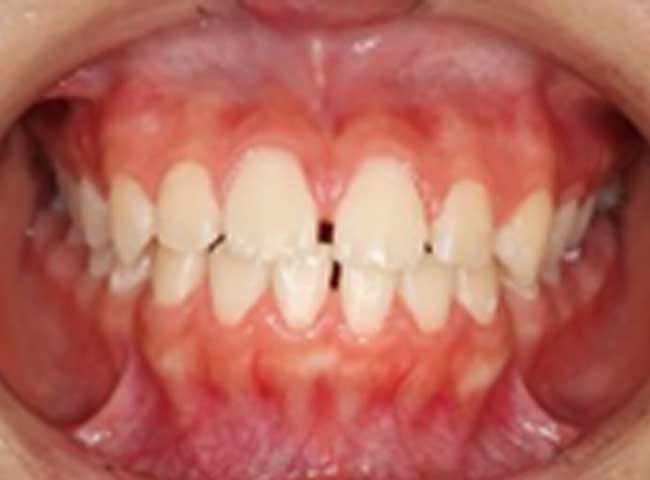

よくあるお悩みの例

CASE